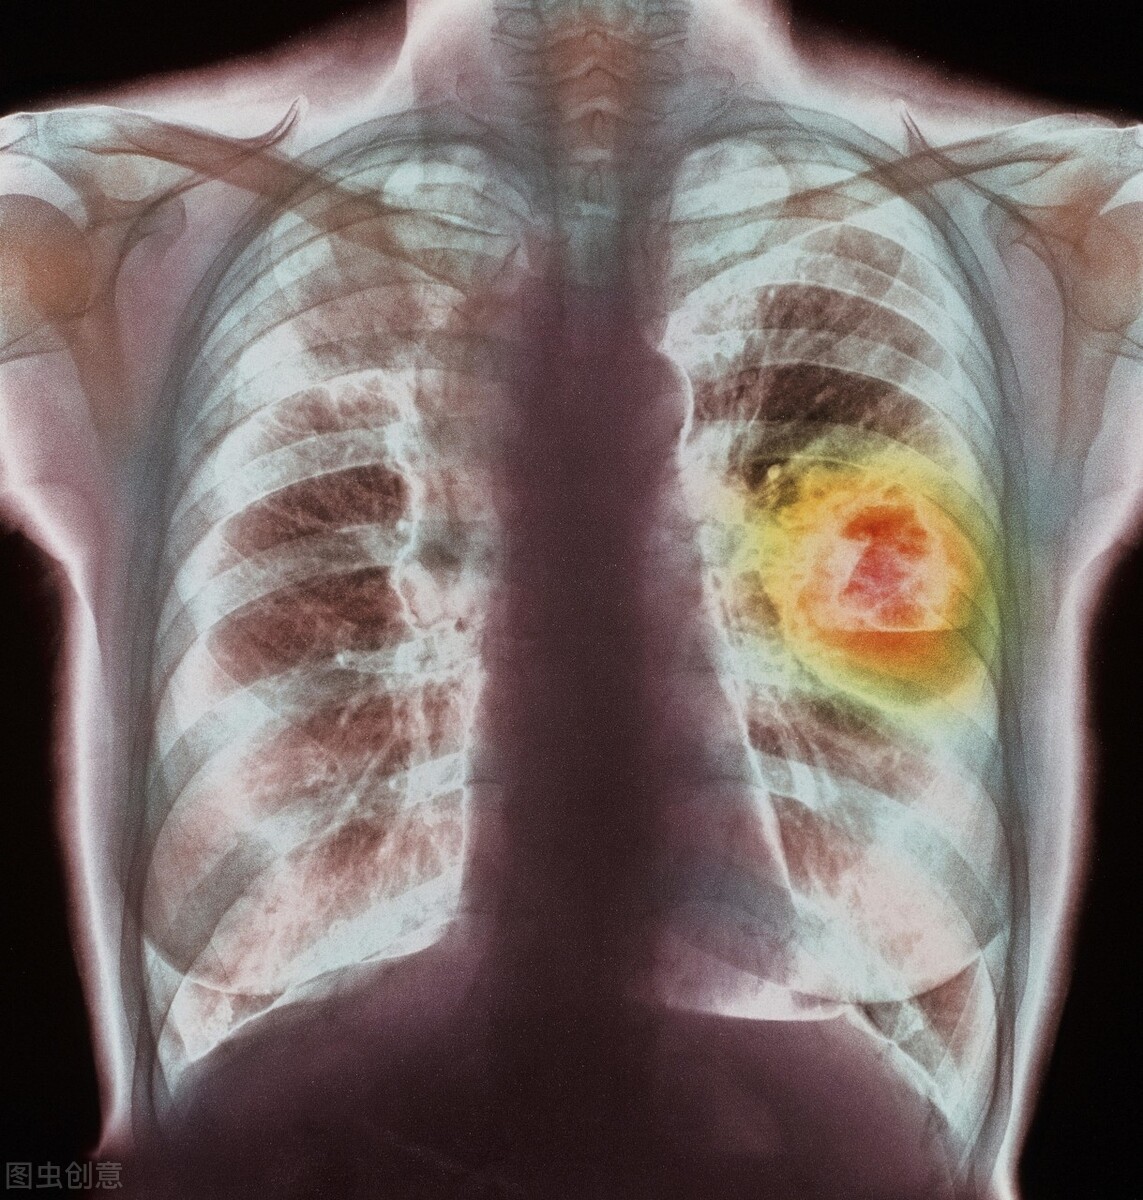

肺癌是致死人数达到最高的癌症,是全球经济第一大恶性循环肿瘤,患病率和致死率均令人感到非常恐怖。你可能知道吸烟会导致肺癌,但这只是故事的一小部分。对于企业预防和治疗这种致命疾病,还有太多我们需要进行了解的。

1.早期肺癌几乎没有症状

你很可能会错过肺癌的症状,因为症状直到癌症发展才出现,这就是为什么许多被诊断为肺癌的人会转移癌。通过这些症状进行确诊的肺癌有7%已是第四阶段,并且具有不可治愈。但不管我们怎样,如果你有反复出现呼吸道病毒感染、持续有效咳嗽,肩背或胸部进行疼痛、呼吸系统困难、声音嘶哑或气喘,或疲惫,需格外当心。